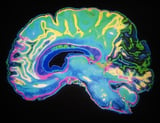

Researchers at The University of Osaka have developed a minimally invasive brain recording technique that uses ultra-thin wire electrodes inserted into cortical and deep cerebral veins via a catheter, achieving high-fidelity recordings comparable to traditional methods.

This innovative approach successfully captures brainwaves from both superficial and deep brain regions in pig models, enabling precise monitoring of brain activity.

By allowing access to deep brain regions non-invasively, this method opens new possibilities for brain monitoring, especially for areas previously difficult to reach without invasive surgery.